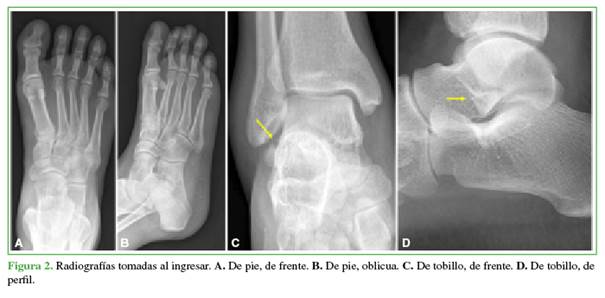

Había sufrido un trauma de tobillo derecho por una caída en una motocicleta de enduro 20 días antes. Fue evaluado en un Servicio de Urgencia el día del accidente donde le tomaron radiografías (Figura 2). Sin un diagnóstico de certeza se le indicó inmovilización con bota walker y restricción de la carga de peso. Fue examinado nuevamente a los siete días del trauma, se le solicitó una resonancia magnética de tobillo y pie (Figura 3) y se le indicó fisioterapia y descarga progresiva del peso. El dolor aumentó progresivamente, y el edema y la impotencia funcional persistían, por lo que decidió buscar una segunda opinión.

En las proyecciones de pie, de frente y oblicua, no se observan imágenes compatibles con lesiones traumáticas.

En la radiografía de tobillo, de frente, se visualiza una solución de continuidad en el contorno lateral distal del cuerpo del astrágalo (Figura 2C, flecha amarilla). La proyección de perfil del tobillo muestra una incongruencia en el reborde anterior del proceso lateral del astrágalo con pérdida de su contorno en forma de V simétrica (Figura 2D, flecha amarilla).